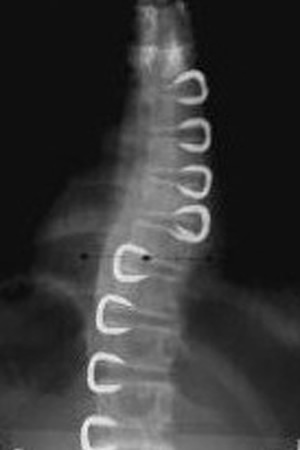

Grafilerle Skolyoz